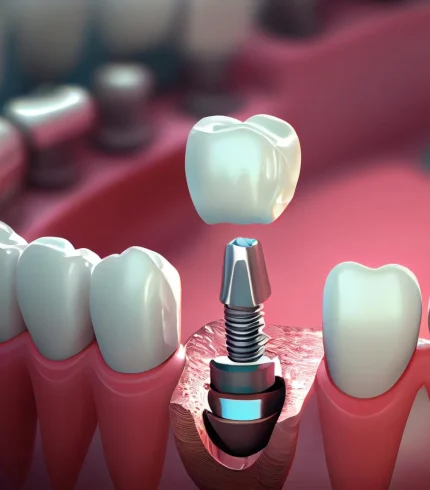

Çene Kisti Operasyonları yapılırken kist uygulanabiliyorsa tek parça halinde alınmaya çalışılır. Büyük ölçekli kistler önce küçültülür daha sonra cerrahi işlemle alınır. Çene kistleri çene kemiğinde ya da diş köklerinde bulanabilir. Eğer kist diş köklerindeyse operasyon sırasında kist ile ilgili diş ağızda bırakıldıysa dişe kanal tedavisi uygulanır ya da operasyon sırasında diş çekildiyse daha sonra ilgili dişe implant tedavisi uygulanır. Operasyon sonrasında bu süreç hem cerrah hem de hasta tarafından dikkat edilmesi bir dönemdir.